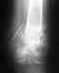

Re: перелом 5 плюсневой кости

послал Alexander Chelnokov 04 Апрель 2011, 08:31

Здесь нельзя утверждать однозначно, что без операции не обойтись. Может срастись и так. Если к 6-8 неделям не будет сращения, то про операцию более предметно стоит подумать.